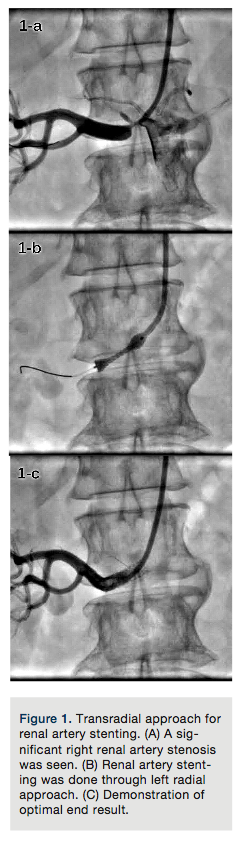

TRA for iliac artery stenting. Approximately one-third of obstructive lesions in peripheral arterial occlusive disease affect the aortoiliac segment.17,45 Iliac artery obstructions have traditionally been treated with open surgery. However, percutaneous transluminal angioplasty (PTA) with stenting has emerged as a less invasive alternative treatment and has proven an effective technique for the treatment of patients with focal iliac artery stenosis.17,20-22 Although TFA is time tested and preferred, TRA is a good alternative approach.17,20-22,45

The left radial is a preferred approach, because it eliminates extra length and tortuosity of the aortic arch, allowing relatively easy tracking and deployment of a long 6Fr sheath.

After obtaining left radial access with a 5Fr introducer sheath, an internal mammary artery catheter is advanced over a long (300cm) .035-inch guidewire into the descending aorta and then the entire system is exchanged for a long (usually 100cm or 110cm) 6Fr introducer sheath. The sheath is positioned at the ostium of the culprit common iliac artery or in the distal aorta just above the bifurcation; the procedure is then performed in the usual fashion (Figure 2A).

Depending on operator experience and hardware availability, balloon-expandable or self-expandable stents can be chosen (Figures 2B and 2C).